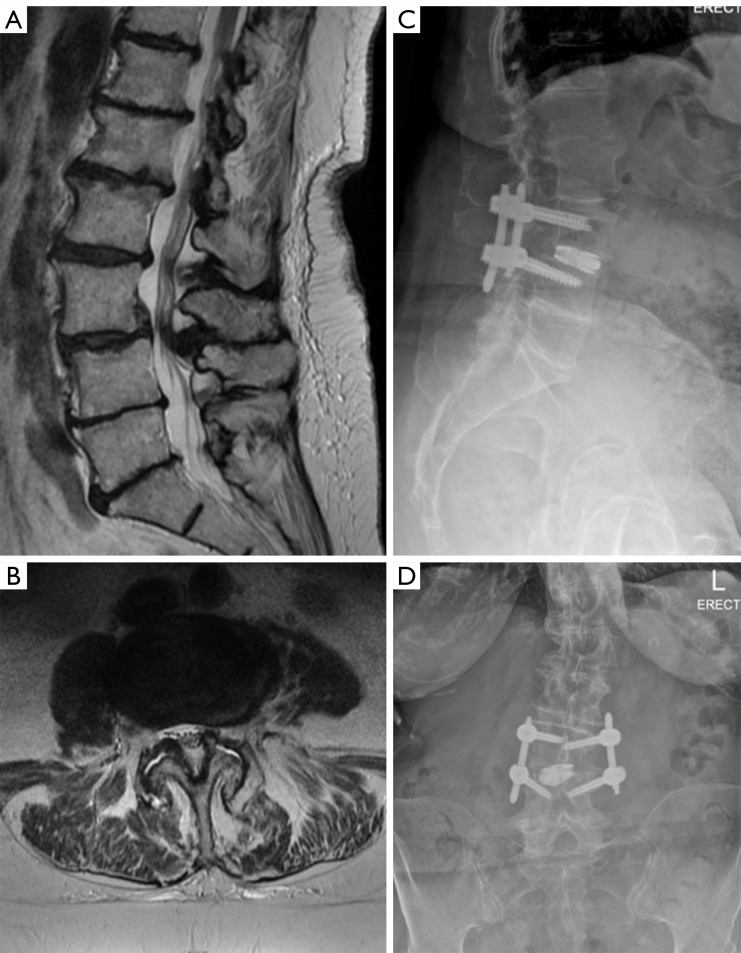

Abstract Image